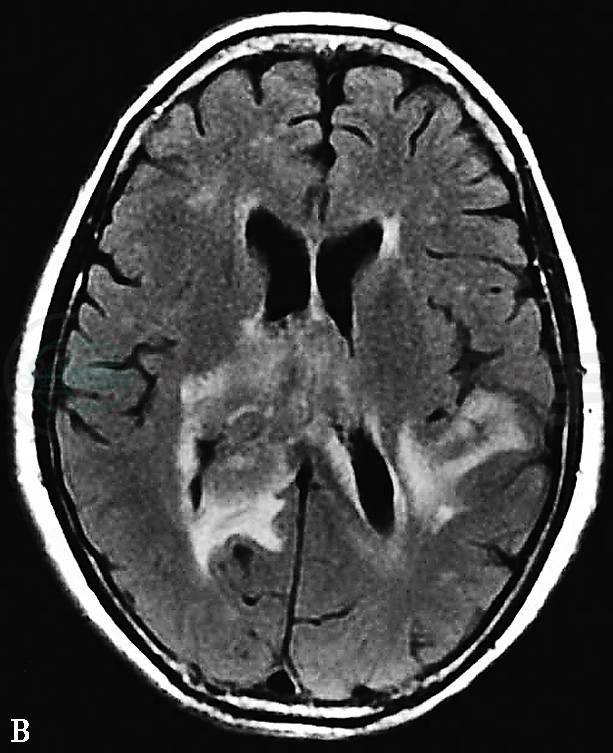

图2 2009年7月头颅MRI:FLAIR像显示(A)双侧颞叶、(B)胼胝体压部及双侧侧脑室内多发异常高信号影;(C、D)增强扫描显示病灶明显不均匀强化

2009年7月头颅MRI:双侧颞叶、右侧丘脑及邻近右侧侧脑室三角区旁、胼胝体压部及双侧侧脑室均可见异常信号,T1WI呈等信号,T2WI稍高信号,FLAIR高信号,病变周围可见不规则水肿区;增强扫描病灶呈明显不均匀强化,中线结构略向左移(图3)。